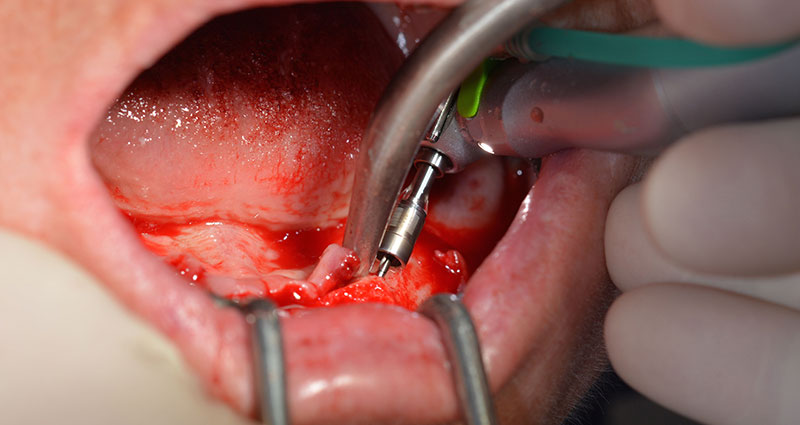

This corresponds to the next preset position in the Implantmed. Here we see the W&H contra-angle handpiece being held at a 45° angle to mesiocaudal in the region of 45 in order to preserve the mental nerve. The mental foramen is used as the anatomic reference for all drilling in this region. The subsequent holes were drilled at a reduced speed of 300 rpm (Fig. 10 and 11).

W&H contra-angle

Fig. 10

speed of 300 rpm

Fig. 11